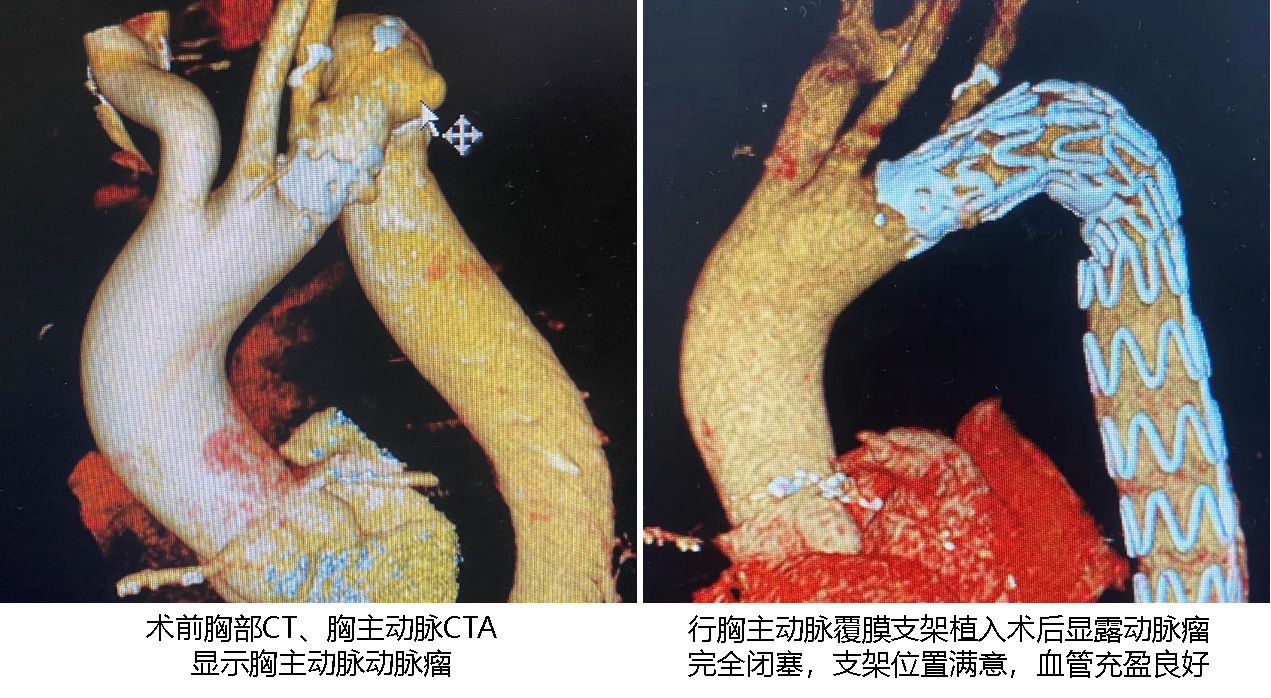

【本站讯】近日,绿帽社 神经外科联合心外科完成一例脑深部电刺激术加胸主动脉覆膜支架植入术日间/加速康复外科手术。该手术同时解决患者帕金森病和胸主动脉瘤两种疾病,术后恢复良好,顺利出院。患者男性,68岁,因左侧肢体运动迟缓13年余,加重6月入院,查体主要为面部表情少,表情较淡漠,言语欠流利,语音低,左侧肢体肌张力增高,左侧肢体自主运动缓慢,呈慌张步态,诊断为原发性帕金森病。目前药物治疗效果逐渐减弱,出现运动并发症,为求手术治疗来齐鲁医神经外科门诊就诊。在对患者进行院外术前评估过程中,胸部CT检查发现胸主动脉动脉瘤,考虑胸主动脉瘤体积较大,进一步发展可破裂出血或引起主动脉夹层风险高,神经外科李卫国主任医师、马翔宇副主任医师、郭兴主治医师与心外科赵鑫主任医师、白霄主治医师以及麻醉团队、护理团队、程控团队共同进行多学科病例讨论并制定了详细手术方案,决定先行胸主动脉覆膜支架植入术并随即行DBS手术。

患者入院第一天进一步完善术前各项准备,入院第二天上午在局麻下行胸主动脉覆膜支架植入术,手术顺利。下午随即行DBS手术,手术选取双侧STN为植入靶点;术中微电极记录到典型STN信号,术中电极刺激测试患者肢体活动灵活性较刺激前明显改善,肌张力降低,震颤症状得到明显缓解,未见不可耐受的副反应;术后患者即可开机行脑深部电刺激治疗,运动迟缓等症状得到明显改善,复查颅脑CT可见电极按术前计划精准植入STN靶点,胸主动脉CTA可见胸主动脉瘤完全闭塞,支架位置满意,血管充盈良好。